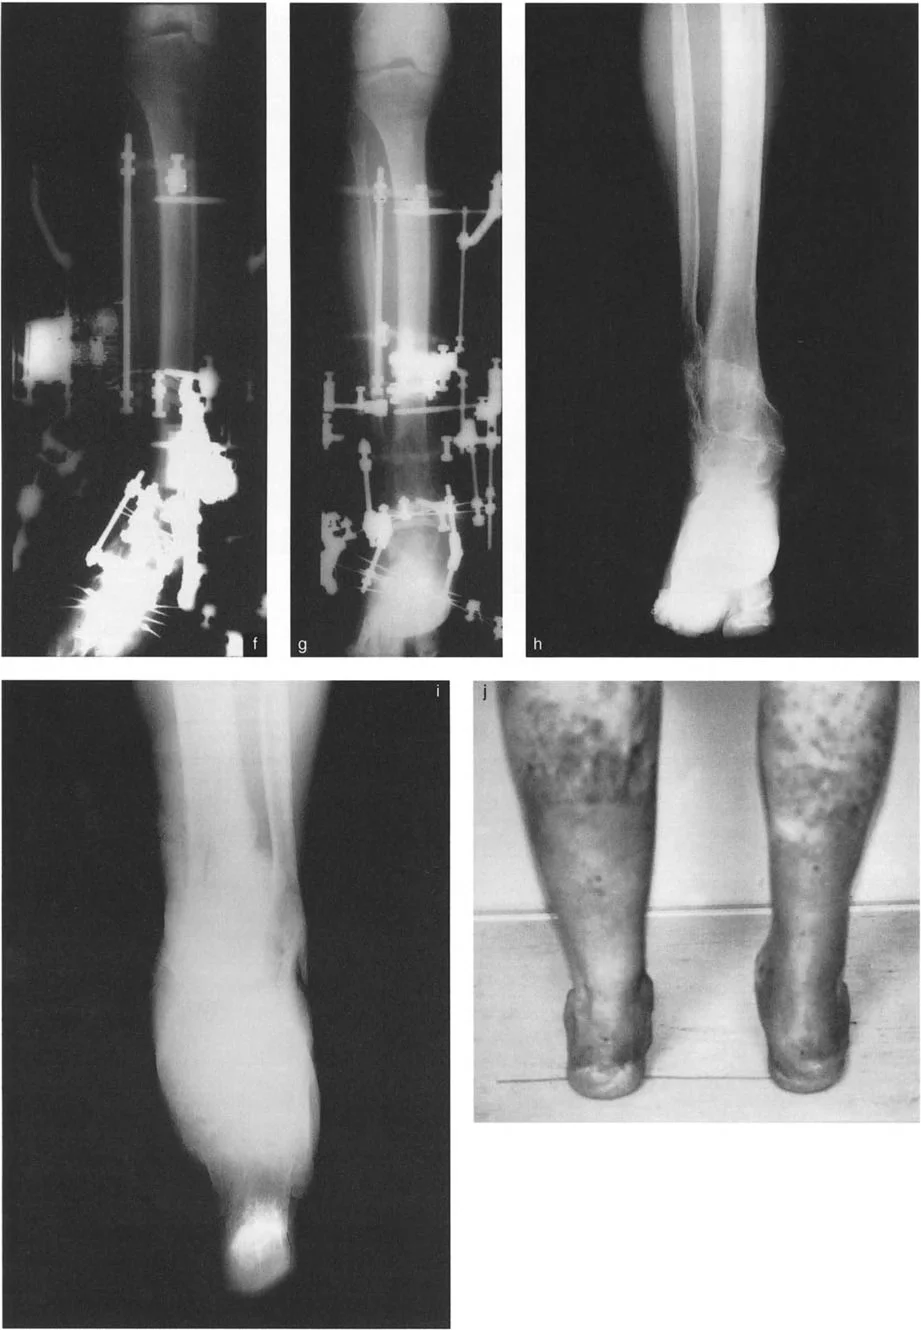

أنواع جراحات قطع العظم فوق الكاحل (Supramalleolar Osteotomy)

جراحة قطع العظم فوق الكاحل (SMO) هي الإجراء الأكثر شيوعًا لتصحيح تشوهات قصبة الساق البعيدة. تتضمن هذه الجراحة قطعًا دقيقًا في عظم الساق (القصبة) فوق مفصل الكاحل مباشرة، ثم إعادة محاذاة العظم وتثبيته في الوضع الصحيح. هناك عدة أنواع من هذه الجراحة:

1. قطع العظم الإسفيني الفاتح (Opening Wedge Osteotomy):

• يتم عمل قطع في العظم ثم فتح فجوة صغيرة فيه. تُملأ هذه الفجوة عادةً بترقيع عظمي (من جسم المريض أو من متبرع).

• المميزات: يحافظ على طول الطرف، وهو مفيد إذا كان المريض يعاني أيضًا من اختلاف في طول الساقين.

• العيوب: يتطلب ترقيعًا عظميًا، ويستغرق وقتًا أطول للالتئام، وقد يزيد من توتر الأنسجة الرخوة حول العظم.

2. قطع العظم الإسفيني المغلق (Closing Wedge Osteotomy):

• يتم إزالة قطعة صغيرة من العظم على شكل إسفين، ثم يتم تقريب أطراف العظم وربطها معًا.

• المميزات: يوفر استقرارًا عاليًا، ويسمح بالاتصال المباشر بين العظام، مما يسرع الالتئام ويسمح غالبًا بتحميل الوزن مبكرًا.

• العيوب: يؤدي إلى تقصير طفيف في الطرف، وهو ما قد لا يكون مرغوبًا في بعض الحالات.

3. قطع العظم القوسي البؤري (Focal Dome Osteotomy):

• يتم عمل قطع منحني في العظم، مما يسمح بتصحيح